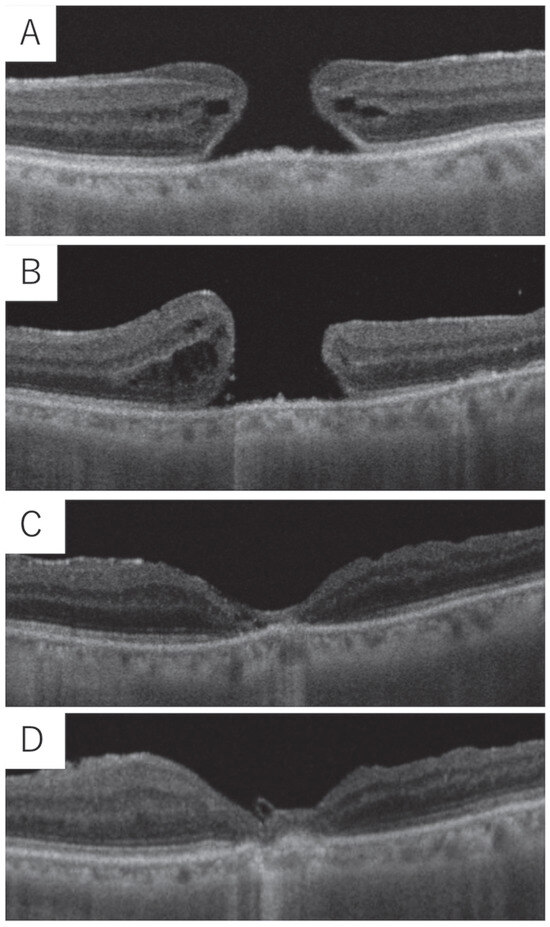

Figure 1

Background/Objectives: Spontaneous macular hole closure is a rare phenomenon, with lamellar hole epiretinal proliferation (LHEP) frequently implicated as a potential mechanism. This study aims to analyze the presence of LHEP in patients with full-thickness macular holes (FTMHs) or lamellar macular holes (LMHs) [...] Read more.

Background/Objectives: Spontaneous macular hole closure is a rare phenomenon, with lamellar hole epiretinal proliferation (LHEP) frequently implicated as a potential mechanism. This study aims to analyze the presence of LHEP in patients with full-thickness macular holes (FTMHs) or lamellar macular holes (LMHs) that closed spontaneously without intervention. Methods: A retrospective longitudinal analysis of optical coherence tomography (OCT) scans was conducted for 73 patients diagnosed with FTMH or LMH in a single institution. Patients with documented spontaneous hole closure were further analyzed for the presence of LHEP, other OCT findings, and clinical characteristics. Results: Of the 73 patients, eight (11%) exhibited spontaneous closure of their macular holes. LHEP was identified in all cases, regardless of hole type (FTMH or LMH). Associated OCT features on diagnosis included VMT in one eye (13%), partial or complete posterior vitreous detachment in seven eyes (88%) and epiretinal membrane in eight eyes (100%). During hole closure, an outer nuclear layer bridge was noted in six eyes (75%). Various extents of outer retinal recovery were noted following closure. After closure, five holes (63%) remained closed without further intervention, while three (38%) reopened and required surgical intervention. Conclusions: Spontaneous macular hole closure is strongly associated with the presence of LHEP, highlighting its potential role in retinal repair mechanisms. While in most patients the spontaneous closure is permanent, surgical intervention may be necessary in cases of hole recurrence. Full article